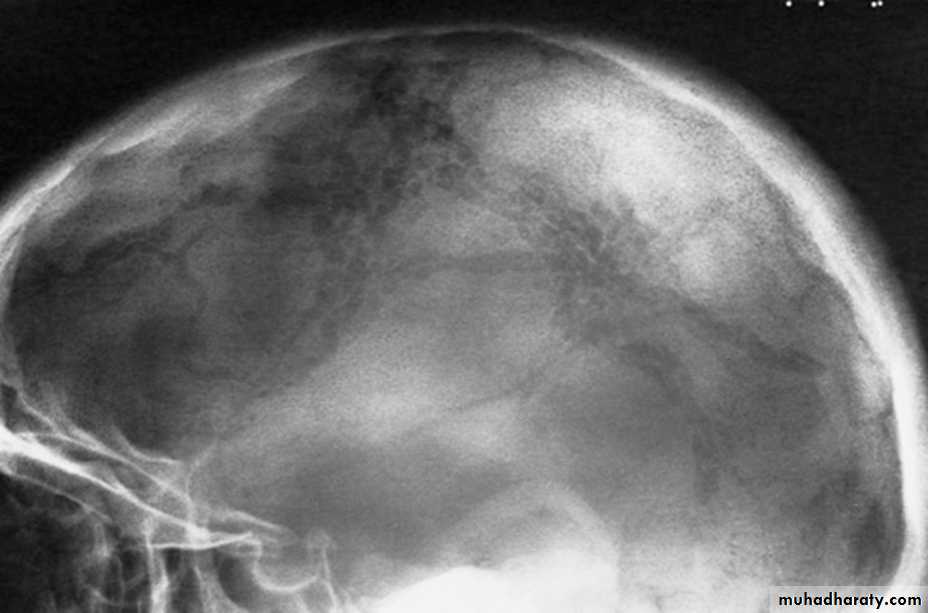

Skull X-rayBony configuration and shape

Bone densityAny Lytic lesion

Any fracture

Any calcification

Diploë, pituitary fossa, paranasal sinuses, orbits

The sutures

The normal pituitary fossa as shown in a lateral skull film can vary considerably in size. Normal figures are (length of 11-16 mm and a depth of 8-12 mm)